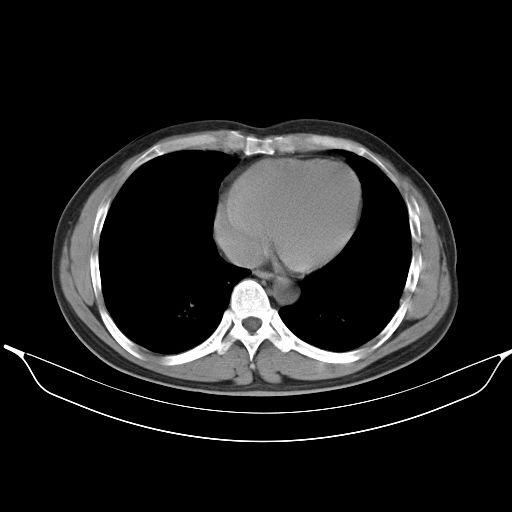

标题: CT25490:男,40岁,体检发现;无其它不适。 [打印本页]

标题: CT25490:男,40岁,体检发现;无其它不适。

考虑右下肺周围性肺癌并肺内多发转移,纵隔淋巴结转移!

支持 !考虑右下肺周围性肺癌并肺内多发转移,纵隔淋巴结转移,(气管前腔静脉后,隆突下,主动脉弓下都有了)

1、均为转移,原发灶不在肺内。2、肺癌肺转移。